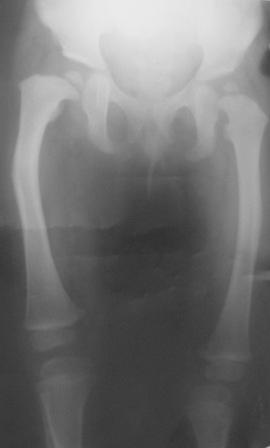

Варусная деформация бедра

Уважаемые коллеги. Осмотрена девочка 2007г.р. При рождении двухсторонная косолапость, двухсторонный врожденный вывых бедер, лечилась консервативно.

В данное время ходит самостоятельно, прихрамывает на прав.ногу, прав. нога укорочена на 3,5см и и находится в положении внутренней ротации 40гр. Леч.врач зав. кафедрой Т.О.мед. института.

Планируется подвертельная деротационно-вальгизирущая остеотомия бедра. Или остеотомия на верщине деформации бедра с удлинением по методу Илизарова.

Добрый день, уважаемый Абдурашид. Начнем с тазобедренных суставов. Какая количественная характеристика параметров этих суставов?Я имею в виду угол антеверзии и шеечно-диафизарный угол, углы горизонтального и вертикального соответствия? Судя по рентгенограмме, у больного в первую очередь весьма проблемен левый тазобедренный сустав, который находится в положении подвывиха!Нога находится в положении внутренней ротации-куда смотрит коленный сустав?Одной из проблем лечения косолапости является торсия костей голени!! При этом стопа смотрит внутрь, но ось коленного сустава нормальна! Если имеет место торсия костей голени, то после остеотомии вы получите коленный сустав, плоскость движений которого будет смещена наружу на величину деротации

Простые расчеты на представленных Вами электронном изображении показывают, что анатомическая разница длины бедер составляет примерно 3.7%,те же цифры получаются и при измерении относительной разницы.

Следовательно , чтобы получить дефицит 3.5 см. необходимо иметь исходную почти метровую длину бедер.

Возможно ошибку в измерении провоцирует не устраненные деформации стоп,которые и являются в данном клиническом случае ведущими.Попробуйте начать с коррекции деформации стоп, а потом вернетесь к оценке состояния т.б суставов и бедер.